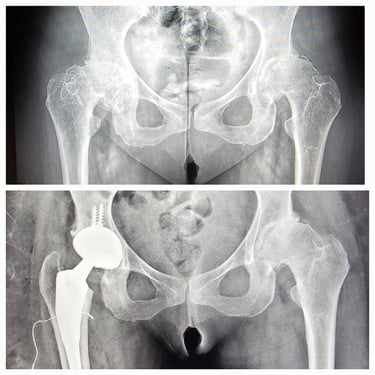

Artroplastia de cadera (prótesis total/parcial).

Cirugía de revisión de cadera y rodilla.

Desgaste articular de cadera y rodilla.